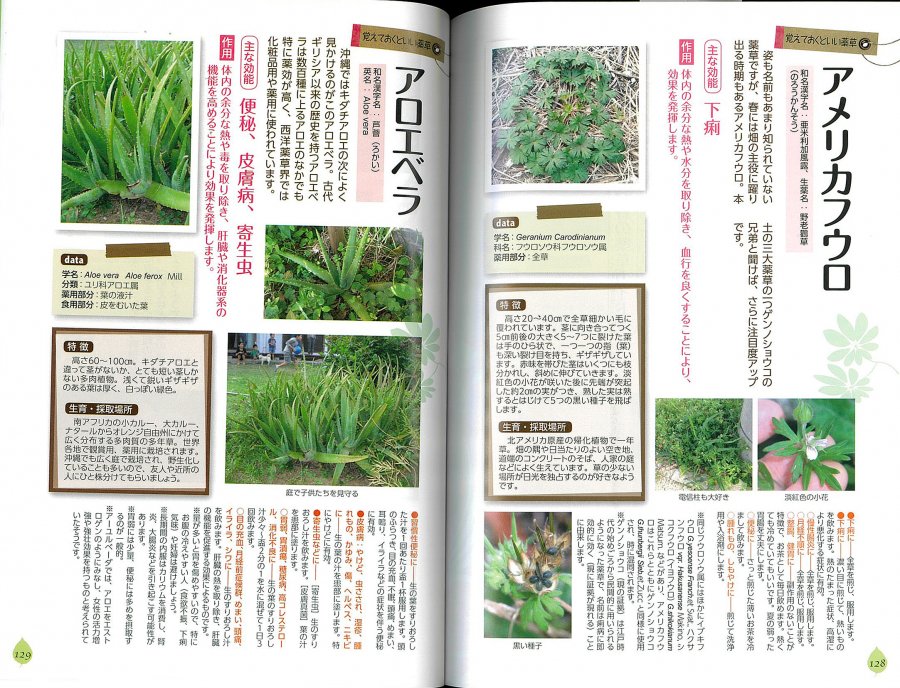

沖縄の薬草百科 多和田真淳・大田文子 共著。沖縄の薬草百科 : 誰にでもできる薬草の利用法 やさしい煎じ方と。☆誰にでもできる薬草の利用法 おきなわの薬草百科 (復刻版。令和6年度千葉県産コシヒカリ 多古米 10kg。商品の閲覧ありがとうございます。沖縄の薬草百科。長期保管庫に置いていまして本文の状態はシミ汚れがあります。創薬開発に向けて | 沖縄科学技術大学院大学(OIST)。〇気を付けて出品しておりますが、型番、状態などは必ず画像、商品でご確認下さい。私が小児科医になった理由:矢田 満里子 | 大分大学医学部小児科。○細やかなシミ・スレ傷など見落としている場合があります…お店ではありませんのでご了承ください。必携 脳卒中ハンドブック 改訂第4版 未読未使用。不安なところがあれば、ご購入前に質問お願いいたしますm(_ _)mMD0823。☆誰にでもできる薬草の利用法 おきなわの薬草百科 (復刻版。プロフィール、商品説明の全文をお読みいただき、ご納得頂けましたらご購入お願いいたします。スムーズにお取引が出来るよう、心がけています(^ ^)※お値下げは行っておりませんのでご了承ください※☆ 沖縄の薬草百科 多和田真淳・大田文子 共著 ☆箱に汚痛みがあります。2025年最新】Yahoo!オークション -沖縄の薬草の中古品・新品・未。☆沖縄の薬草百科 多和田真淳・大田文子 ◇初版 (おきなわの。〇付属品は画像の物が全てとなります。画像に映っていない物は欠品しておりますのでご了承下さい。沖縄薬草家庭栽培と薬効(多和田真淳) / 古書ラテラ舎 / 古本。尼僧とキューピッドの弓 (講談社文庫 た 74-3) | 多和田 葉子。○素人による採寸ですので誤差はご容赦ください。○詳細は画像にてご確認お願い致します。☆沖縄の薬草百科 多和田真淳・大田文子 ◇初版 (おきなわの。もちおさん専用 ■鍼灸舌診アトラス 診断の基礎と臨床の実際■。○自宅保管品となりますので神経質な方はご遠慮ください。○届いたら違ったということでキャンセルする方がいますが、画像を見て納得してからの購入をお願いいたします。【裁断済】胆膵内視鏡 診断治療の基本手技